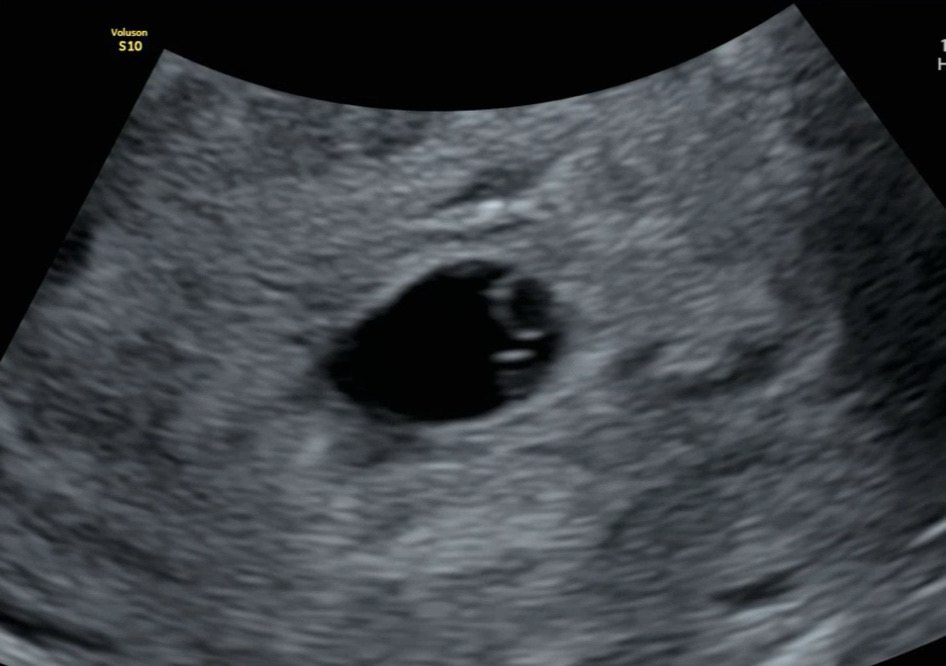

주말에 갈색피비침이 잇어 오늘 걱정되서 병원에 갔어요 초음파보더니 6주1일이라고 하셨고 저번주 수요일에 난황과 아기집1.2cm 봤는데 오늘은 아기집1.7cm로 커지고 난황만 보이고 아기와 심장깜빡임이 안보인다고 아기가 느린거같대요.. 원래 심소듣기로한 이번주 토요일에 아기와 심소 못들으면 고사난자라는데... 6주1일 2일에 배아 못보면 고사난자인가요..? 아기집도 5일만에 5mm자란거면 잘 자란거같은데... 펑펑울면서 서브병원가니 난황아래 보이는 구조물이 아기일수도 있고 아닐수도있다고 너무 일러서 토요일에 초음파가 중요할거같다하시네요 난황아래 보이는 구조물이 아기일 가능성은 없나요..?

엥 난황 아래에 아가아닌가요?? 올챙이같은... 토욜에 아가 잘 보일거에용☺️